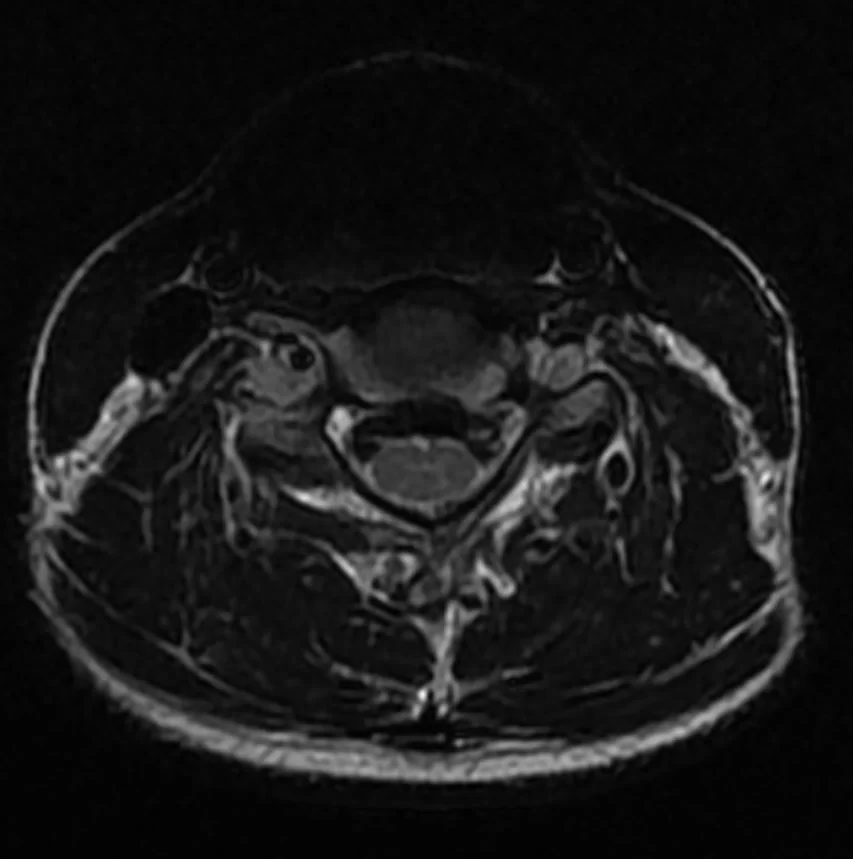

Ο απεικονιστικός έλεγχος έλεγχος με μαγνητική τομογραφία της αυχενικής μοίρας της σπονδυλικής στήλης (ΑΜΣΣ) ανέδειξε κήλη μεσοσπονδύλίου δίσκου στο επίπεδο Α5/6 και ευθειασμό της ΑΜΣΣ.

Διενεργήθη πρόσθια δισκεκτομή Α5/6 και τοποθέτηση τεχνητού δίσκου (Cadisc-C).